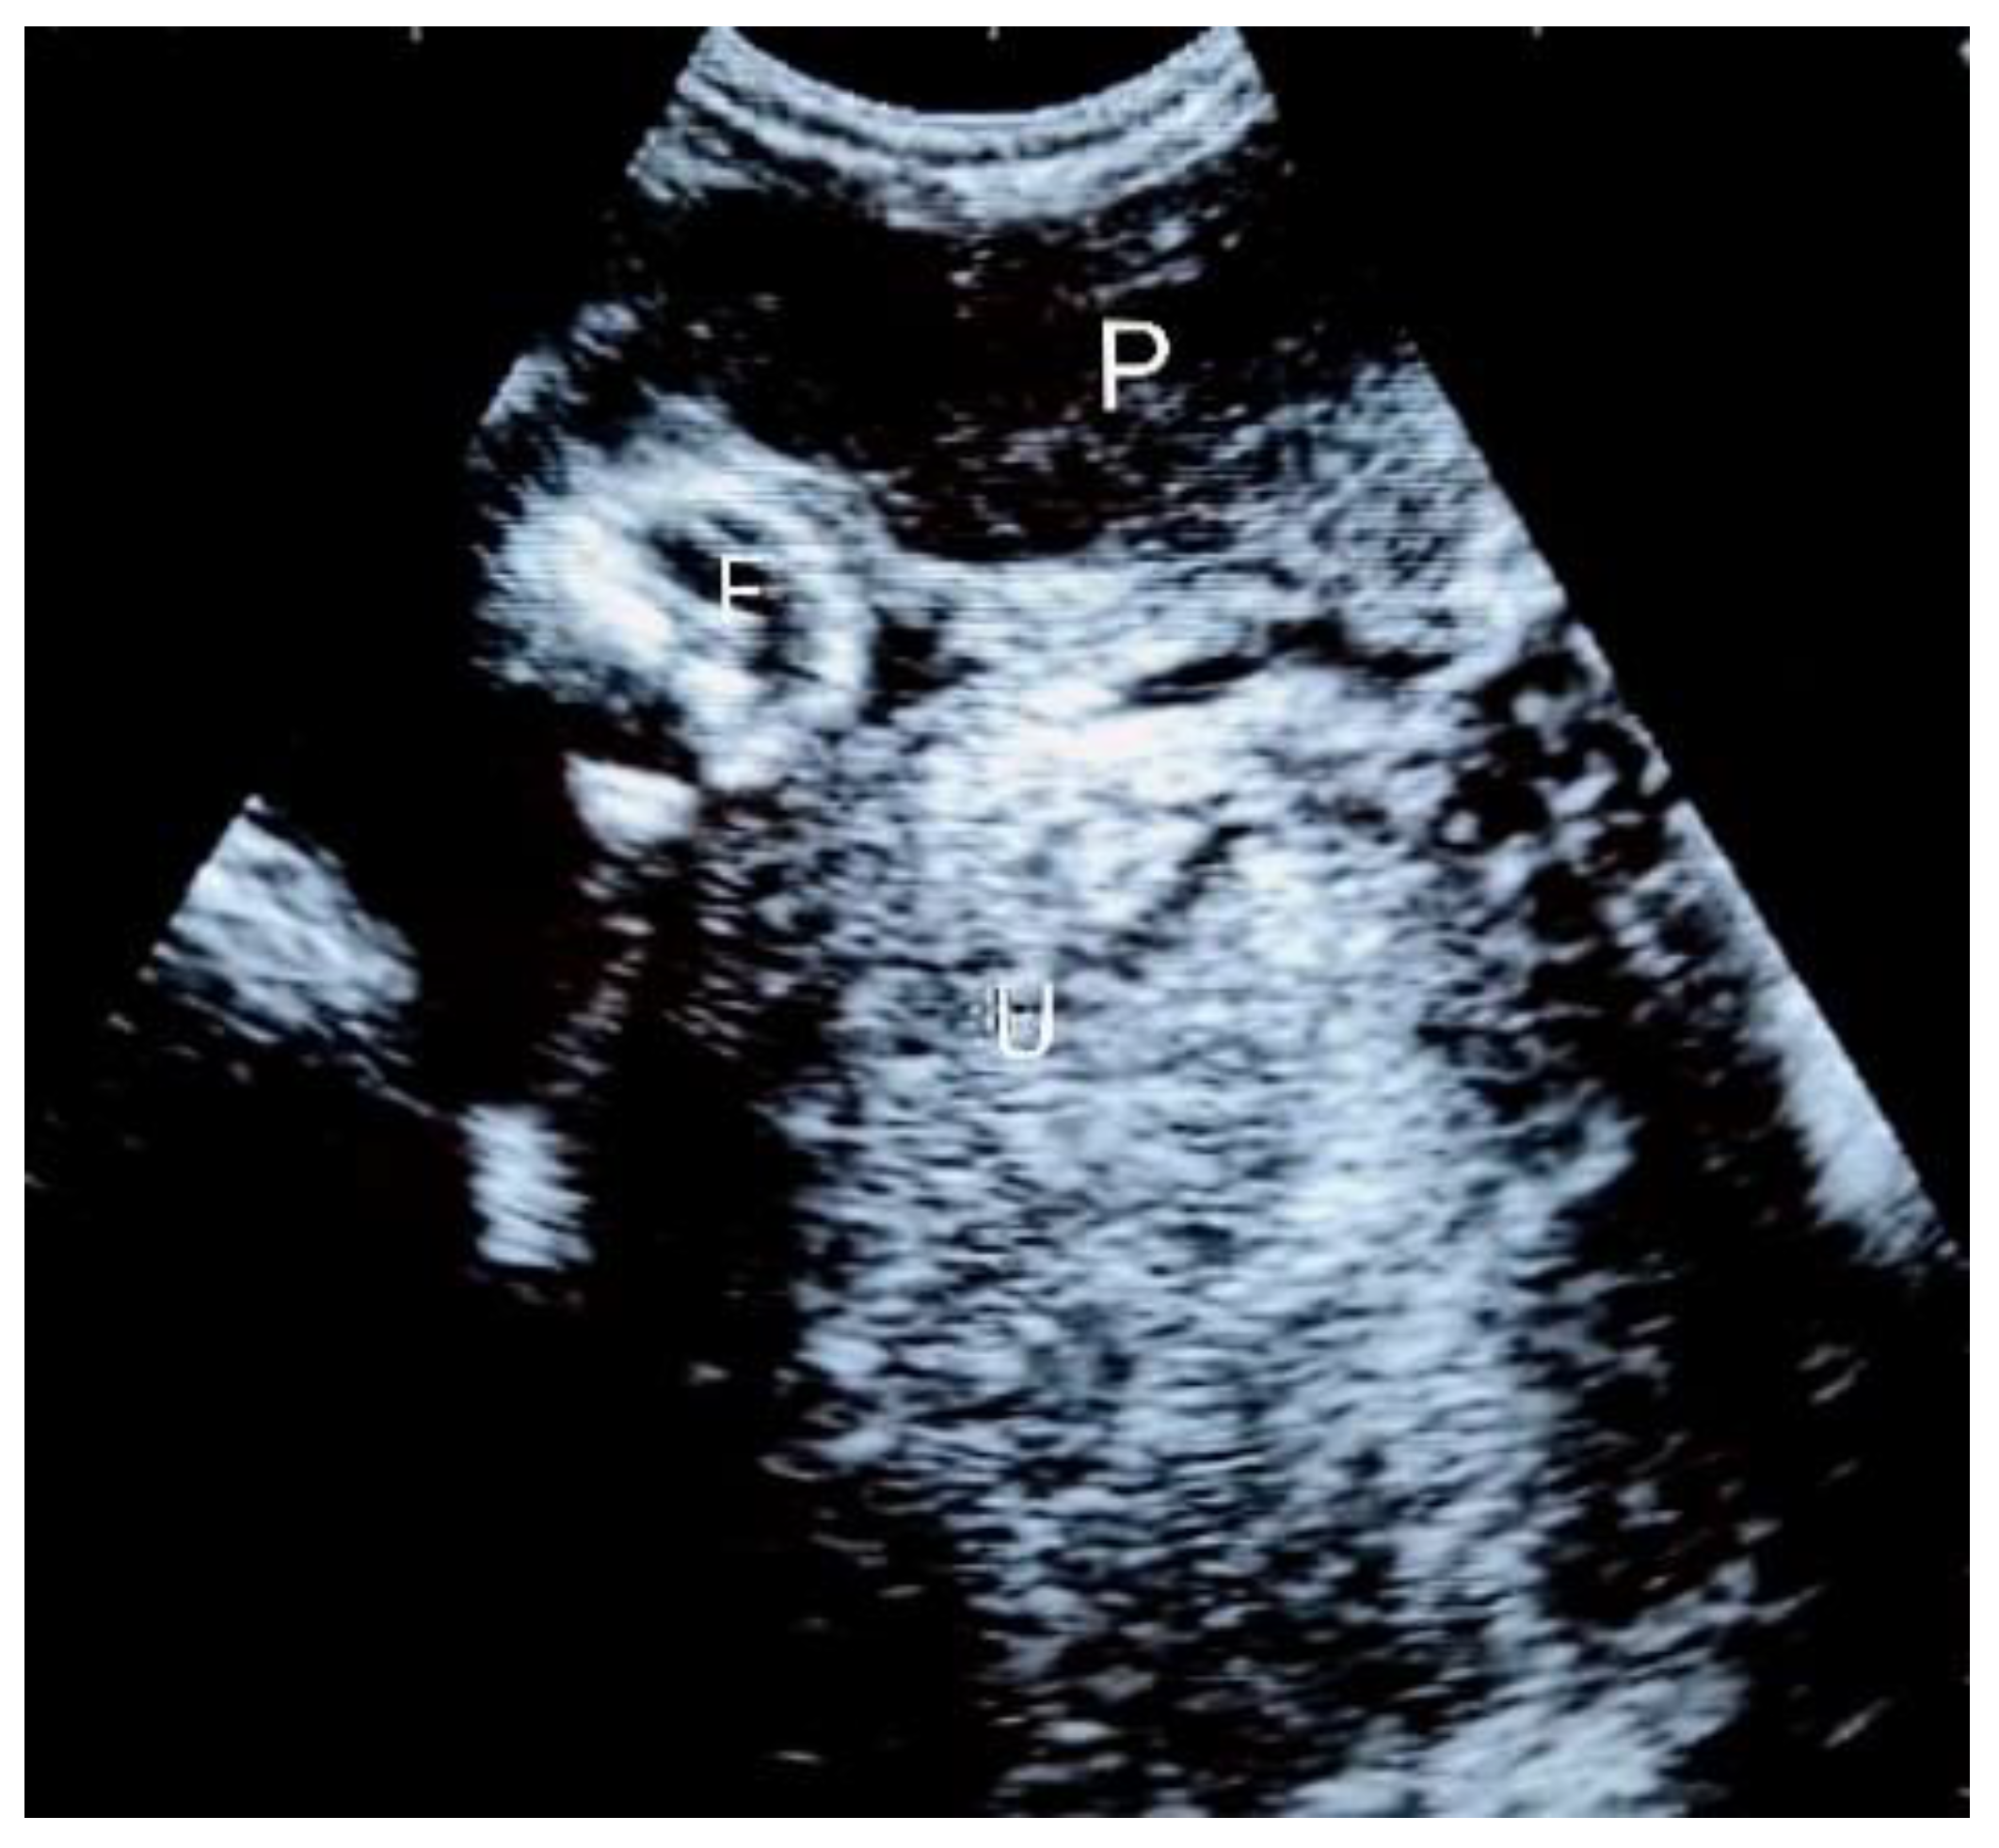

3. Case Presentation